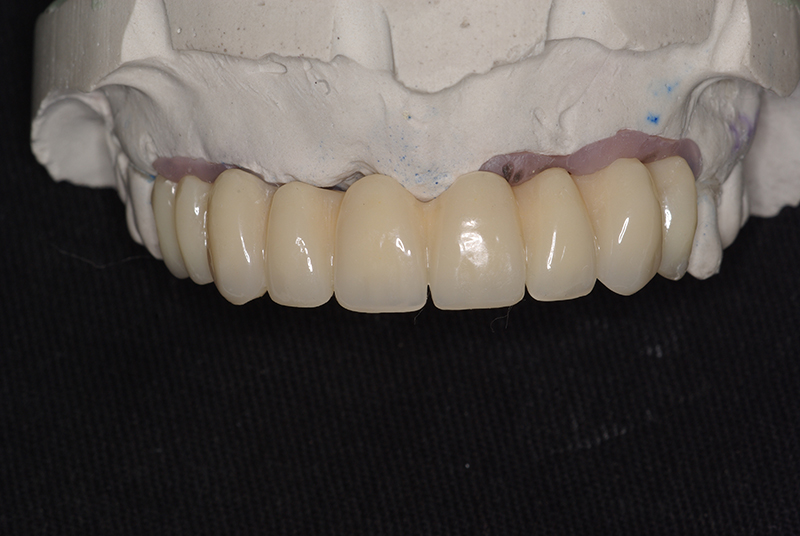

Utilizamos a tecnologia CAD CAM, um sistema avançado que possibilita a confecção precisa das próteses dentárias diretamente sobre os implantes. Esse método inovador garante um ajuste perfeito, um resultado estético superior e proporciona muito mais conforto e durabilidade. Com o CAD CAM, nossos pacientes contam com um processo mais rápido e previsível para alcançar o sorriso desejado.